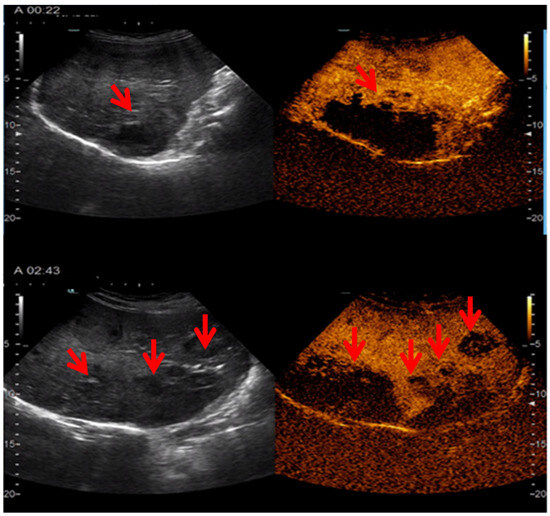

2.5. Imagery Scans